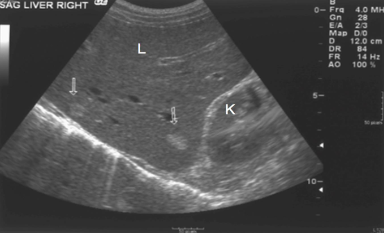

What is the kidney’s echogenicity to the liver?

Isoechoic